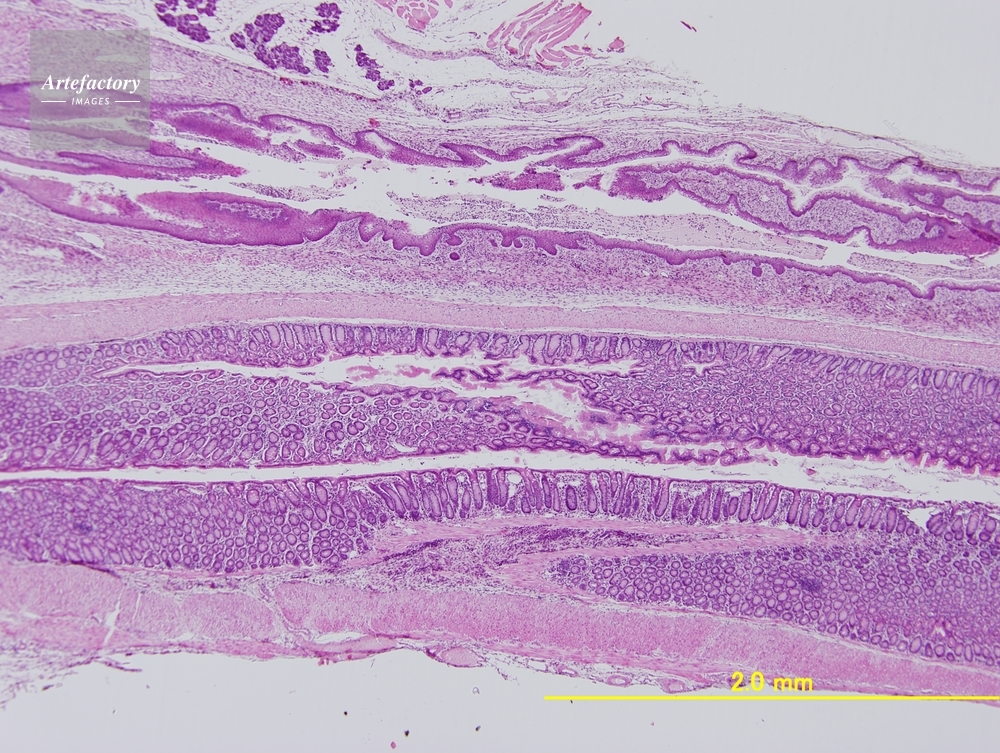

| 作品タイトル | マウス 膣、子宮、直腸 | モデルリリース | なし | |